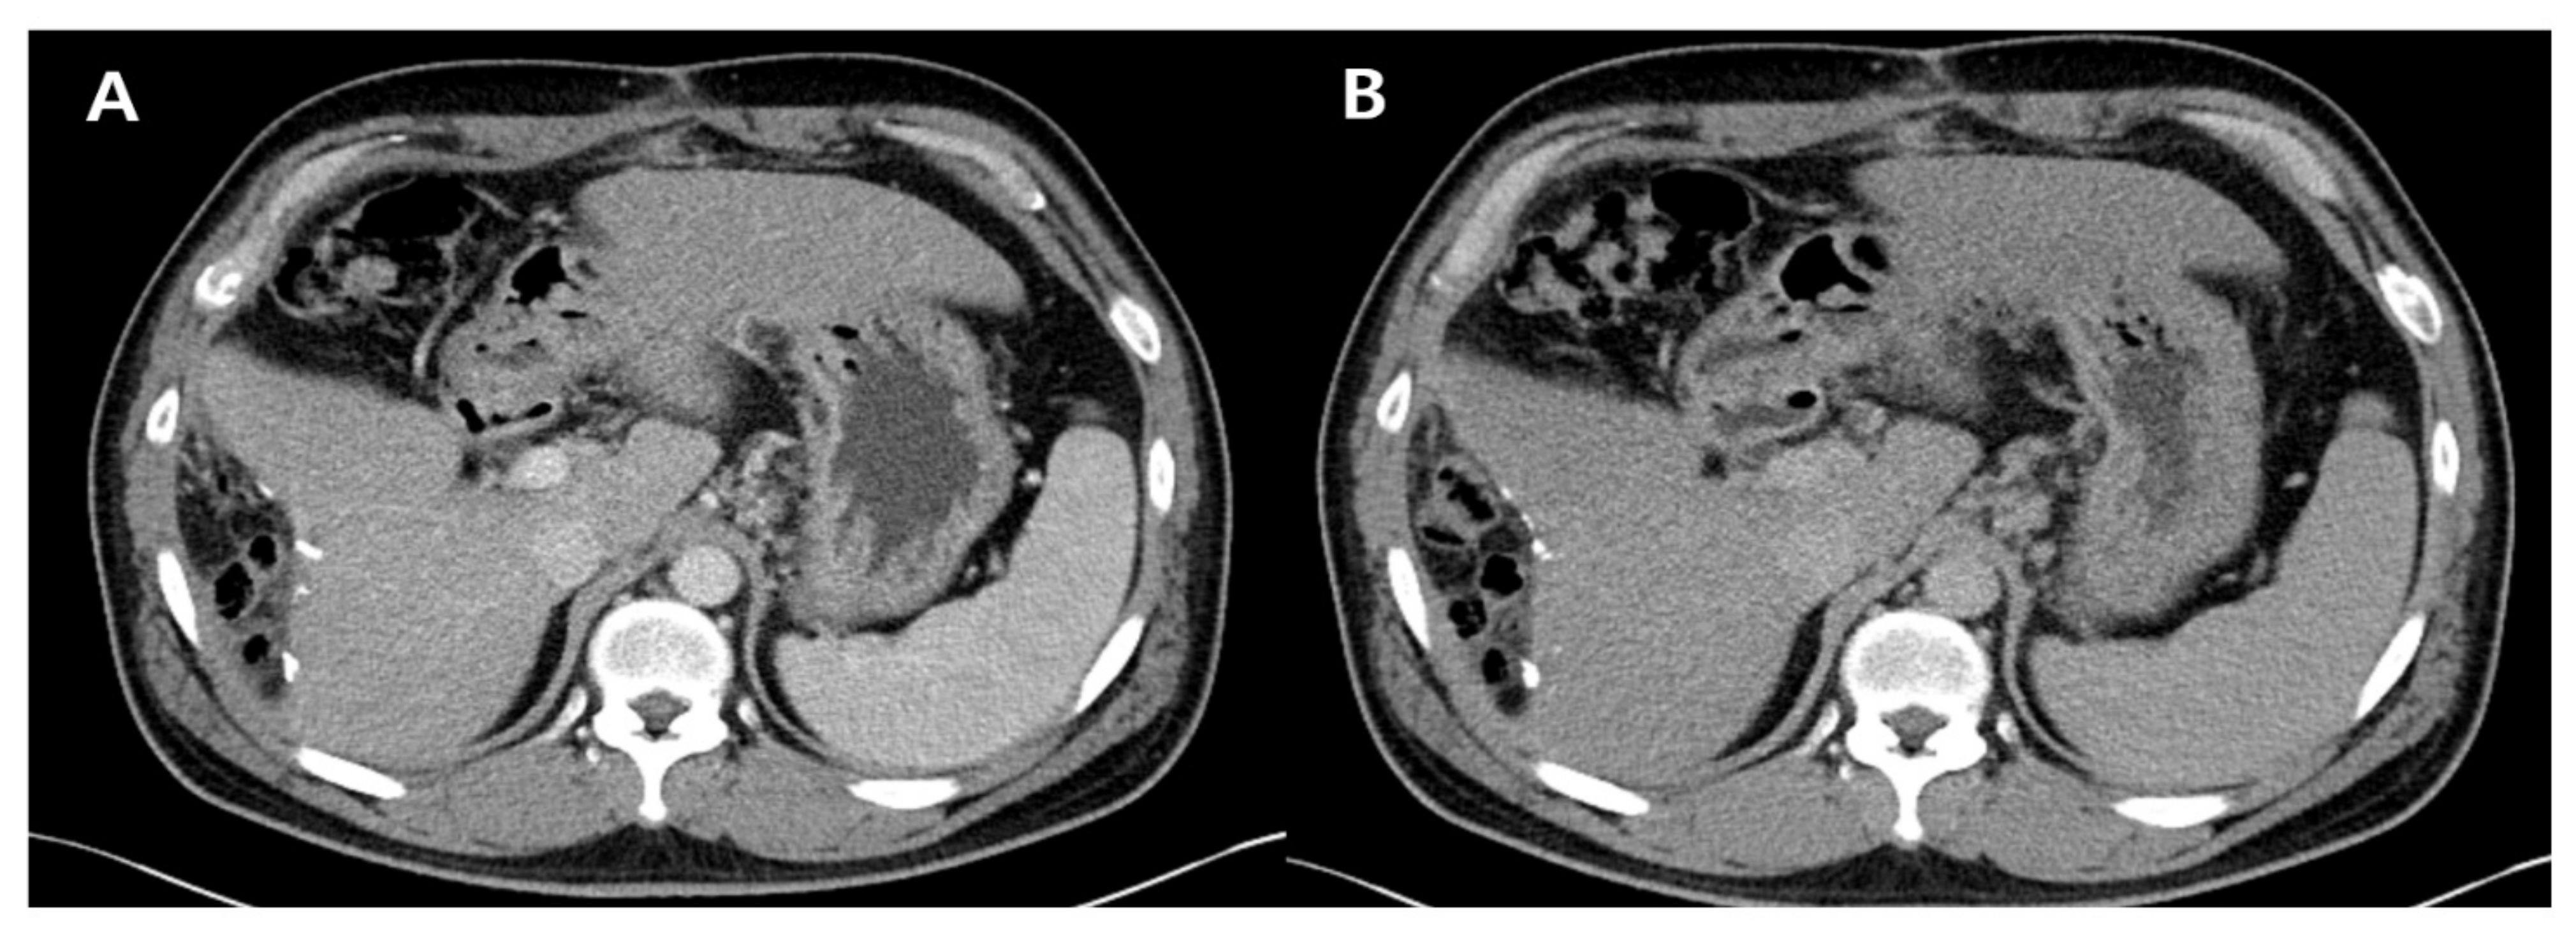

Dynamic T1-weighted MRI revealed a 3-cm-sized, lobulated mass at segment 6, demonstrating hyperintensity in the arterial phase, isointensity in the delayed phase, and hypointensity in the hepatobiliary phase, suggesting the possibility of HCC (Figure 1). Due to the elevated AFP level and the peripheral location of the mass, tumor resection was performed instead of a biopsy.

Figure 1. T1-weighted magnetic resonance imaging reveals an approximately 3-cm-sized, lobulated, hypointense mass in the pre-contrast phase (A), a hyperintense mass in the arterial phase (B), an isointense mass in the delayed phase (C), and a hypointense mass in the hepatobiliary phase (D), at segment 6. The lesion is indicated by white arrows in all phases.